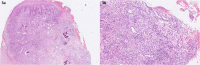

Necrotizing stomatitis is a rare, acute-onset disease that is usually associated with severely malnourished children or diminished systemic resistance. We describe a 1-year-old girl who developed necrotizing stomatitis, vasculitic rash, skin desquamation on the fingers and toes, and persistent hypertension after serologically confirmed SARS-CoV-2 infection. Her laboratory investigations revealed positive IgG anticardiolipin and IgG anti-β2 glycoprotein antibodies, and biopsy of the mucosa of the lower jaw showed necrosis and endothelial damage with mural thrombi. Swollen endothelial cells of small veins in the upper dermis were confirmed also by electron microscopy. As illustrated by our case, necrotizing stomatitis may develop as a rare complication associated with SARS-CoV-2 infection and can be considered as a part of the clinical spectrum of COVID-19 vasculopathy. The pathogenic mechanism could involve a consequence of inflammatory events with vasculopathy, hypercoagulability, and damage of endothelial cells as a response to SARS-CoV-2 infection.